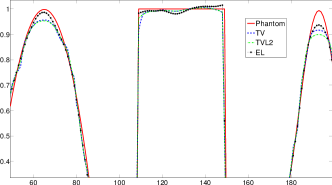

Reconstructed images are presented in Fig. 4. Since CGLS-TV- reconstruction might look more appealing than CGLS-EL we also show the surface representations of reconstructed images (see Fig. 5) and horizontal middle cross-sections (see Fig. 6).

One can notice that CGLS reconstruction is very noisy. CGLS-TV method better suppresses noise, however smooth features are strongly affected by the “staircasing” effect. CGLS-TV- method provides reconstruction with smoother features and CGLS-EL method resolves smooth features even better (e.g. cone-shaped parabola). Although CGLS-EL method performs very well for smooth objects one can notice the wave-like variations of intensity in the background and also at the top of the rectangle (see Fig. 6). This issue can be explained by the properties of our regularizer, in contrast to TV, our penalty does not seek the sparsest solution and does not penalize strongly (pushing to the constant value) a small intensity perturbations. The EL term tends to preserve all sharp edges while uniform noise is smoothed isotropically with the Laplacian. In Fig. 6 one can see that the CGLS-EL method provides better recovery of smooth features while slightly higher (compare to TV and TV-) perturbations visible in uniform areas (the top of the rectangle), however, the edges of the rectangle are defined sharper with the EL penalty.